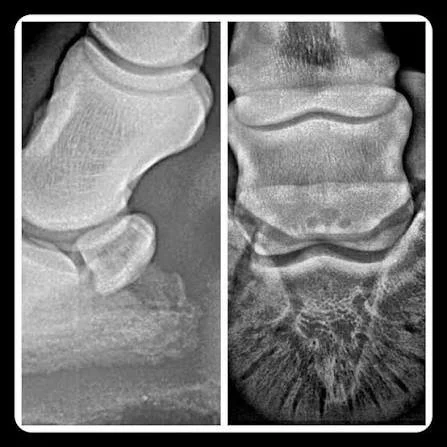

Síndrome Navicular

El síndrome navicular es una de las patologías más dolorosas y limitantes en los caballos, asociada a la región del hueso navicular y sus estructuras adyacentes, incluyendo la bursa navicular y el tendón digital profundo. La tensión excesiva sobre esta zona provoca inflamación, degeneración y dolor crónico, que se manifiestan en cojeras persistentes y pérdida de rendimiento.